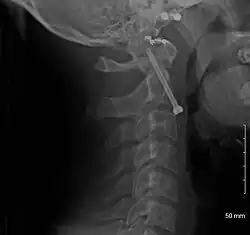

Repair of a dens fracture

A fracture of both pedicles of the axis is termed a Hangman's fracture.

Fractures of the dens are classified into three categories according to the Anderson Alonso system:

• Type I fracture - Extends through the tip of the dens. This type is usually stable.

• Type II fracture - Extends through the base of the dens. It is the most commonly encountered fracture for this region of the axis. This type is unstable and has a high rate of non-union.

• Type III fracture - Extends through the vertebral body of the axis. This type can be stable or unstable and may require surgery.[1]